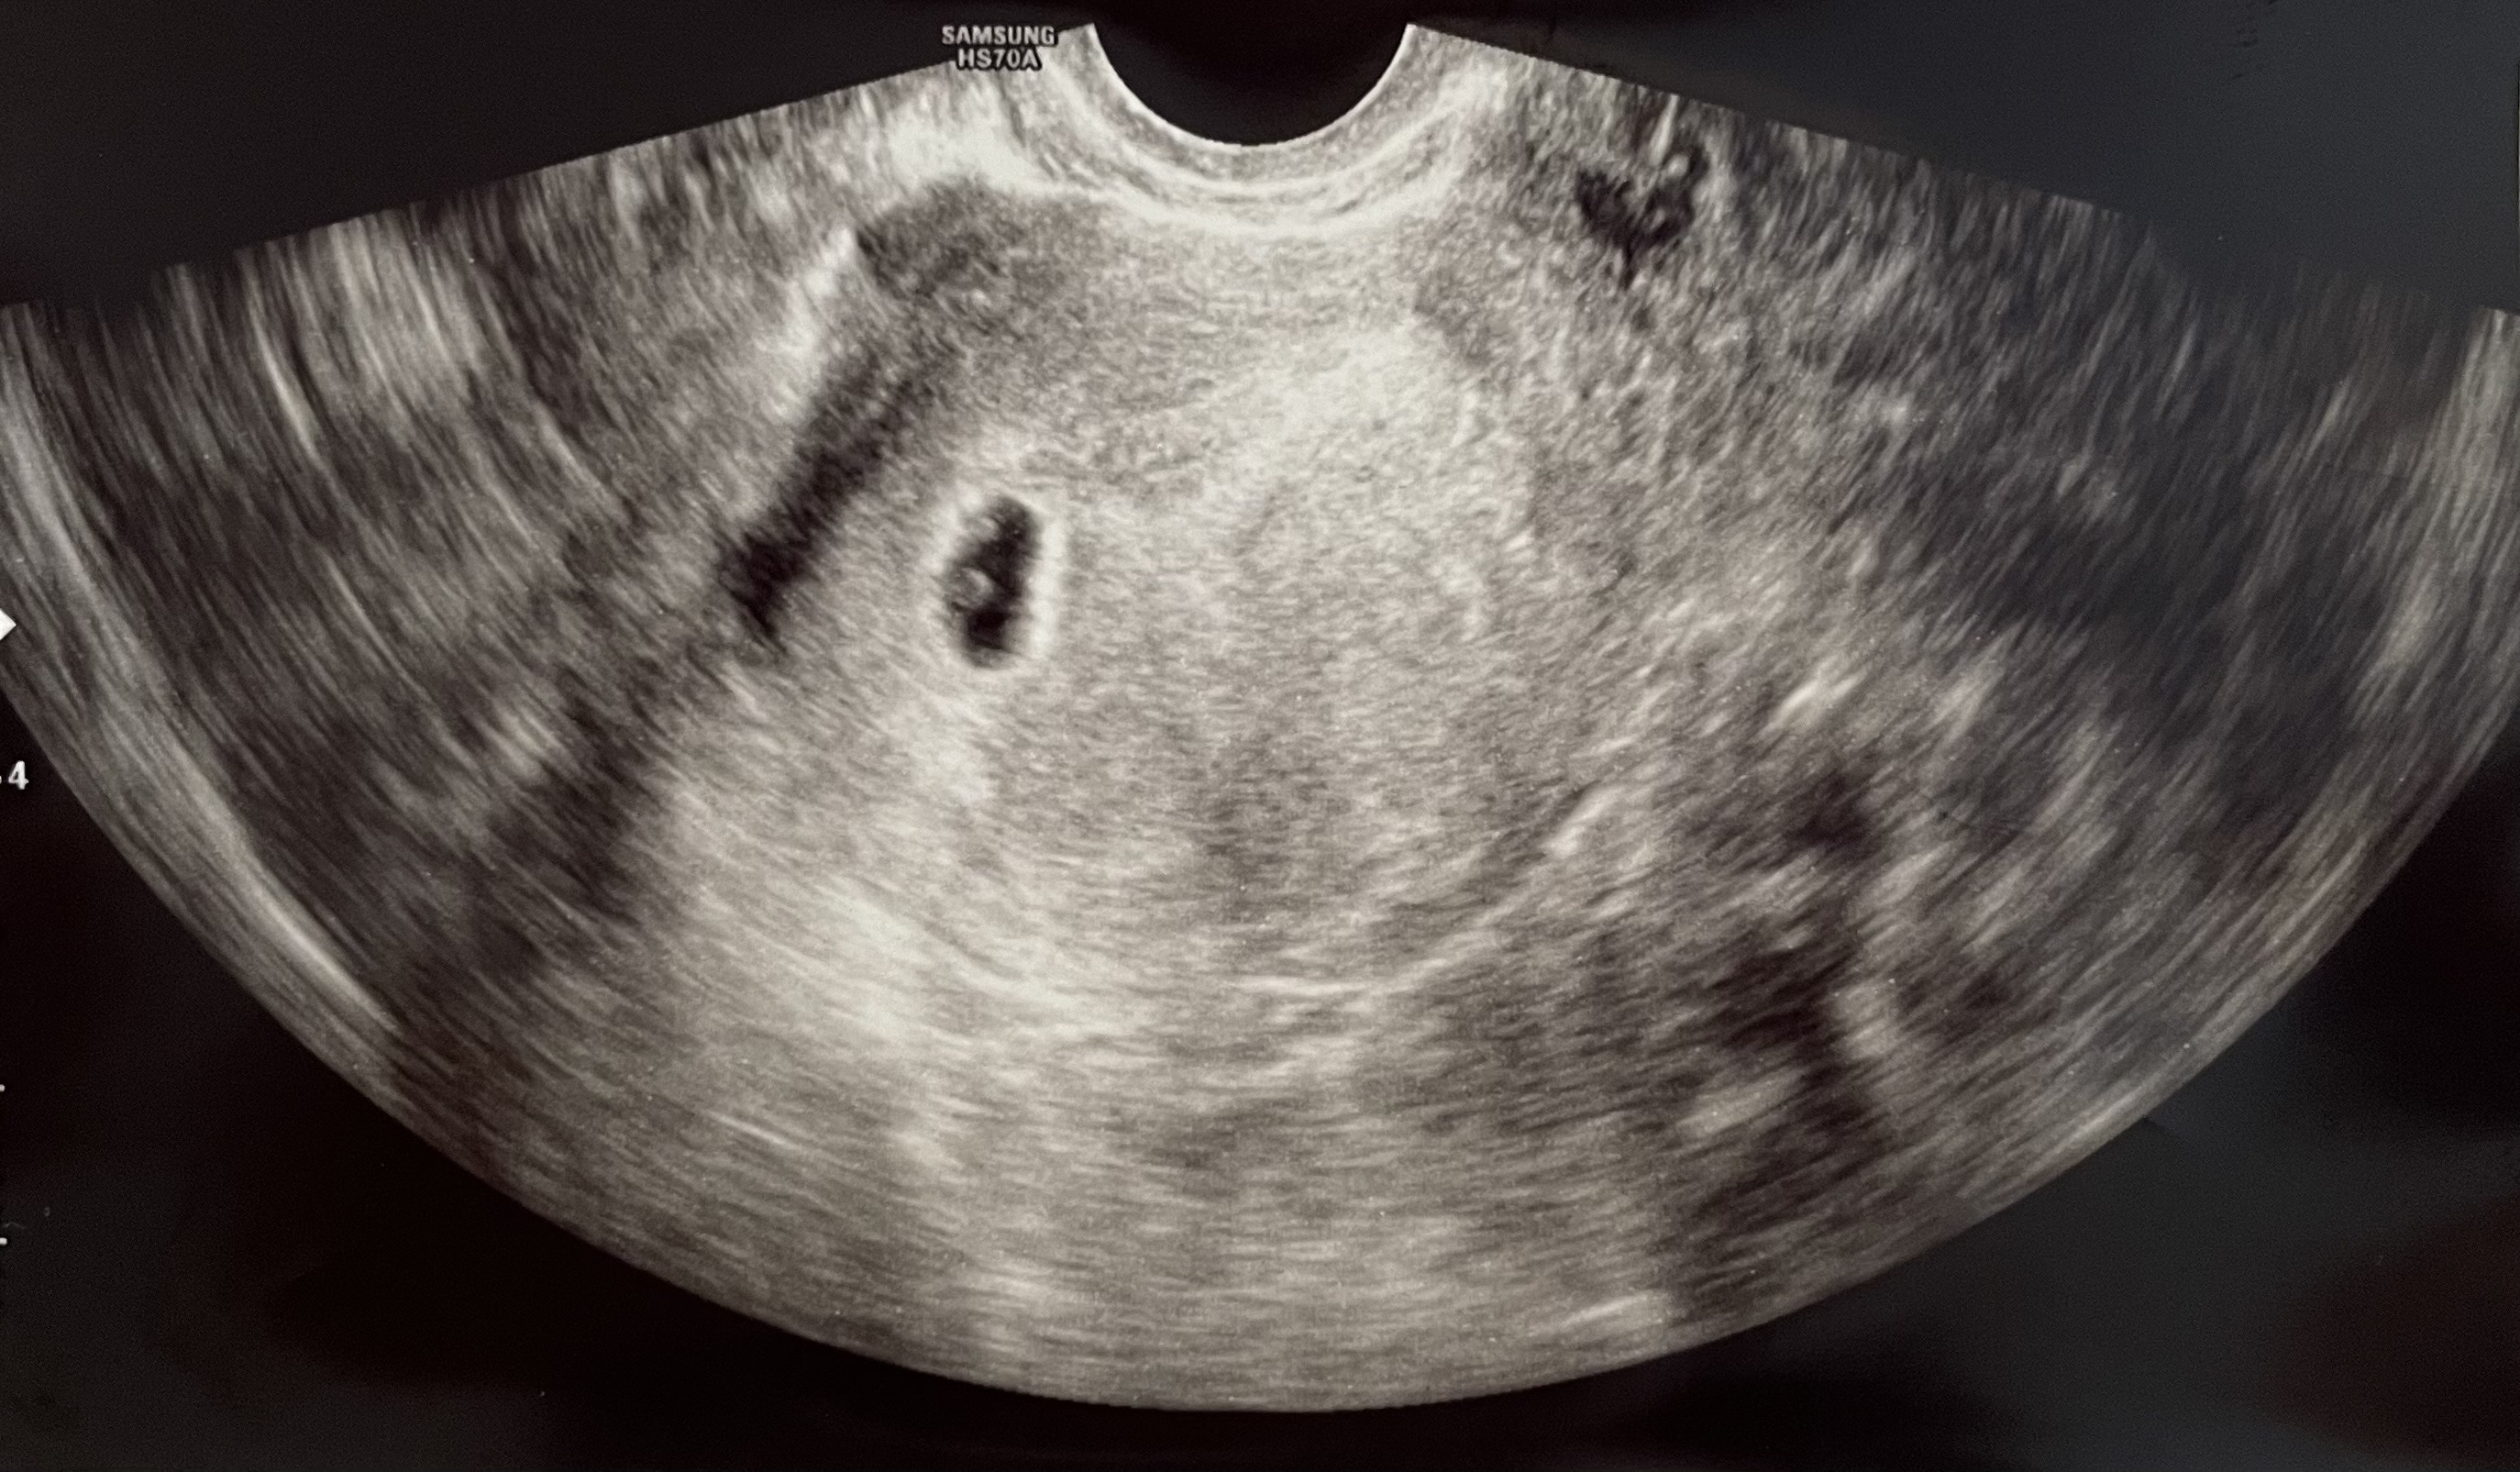

병원에서 임신확인 받고 왔습니다! 5주 2일차 산모예요~~ 선생님께서 아기집도 주수에 맞고 난황 위치도 크기도 좋다고 하셨거든요 선생님과 같이 초음파 봤을땐 난황이 두 개인것 같았지만 따로 말씀은 안드리고 나왔는데 쌍둥이일 가능성은 거의 없다고 말씀해주시긴하셨어요ㅎㅎ 너무 작아 자연 도태될 확률이 높아서 말씀안해주신걸까요? 의사선생님 말씀이 제일 중요하고 전문지식 없이 인터넷 검색하는거 안좋은거 알지만 첨엔 단태아 진단받았다가 7-8주차에 다태아로 바뀐분들도 많다고들어서 초음파 사진 한번 올려봅니다.

일란성이면 아기집하나에 난황이 두개에요! 아기집두개는 이란성!